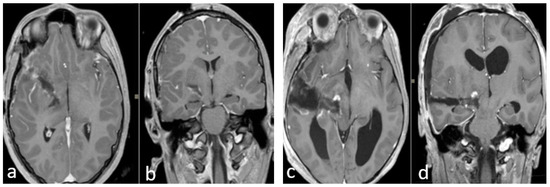

DTI-MRI CST reconstruction combined with nTMS mapping allows for an accurate tridimensional visualization of the cortical spinal bundles and helps the surgeon to choose the safer surgical corridor (Figure 1 and Figure 2).

(I–IV) Neuronavigated transcranial magnetic stimulation pre-op study. (I,II) A 3D reconstruction of the nTMS data that shows cortical maps of the right spinal tract (CST) for the hand (green) and foot (yellow) and its relationship with the thalamopeduncular tumor of Case B. (III,IV): The brain MRI merged with the nTMS data shows that the cortical spinal tract (CST) runs antero-laterally with respect to a right thalamopeduncular tumor.

In the most recent cases (Case A–Case B), the preoperative nTMS was performed to obtain a cortical motor mapping and the cortical spinal bundles reconstruction. The nTMS data confirmed the DTI MRI data for the motor bundles’ displacement, adding functional information about cortical and subcortical motor areas of the mouth, arms and legs (Table 3).